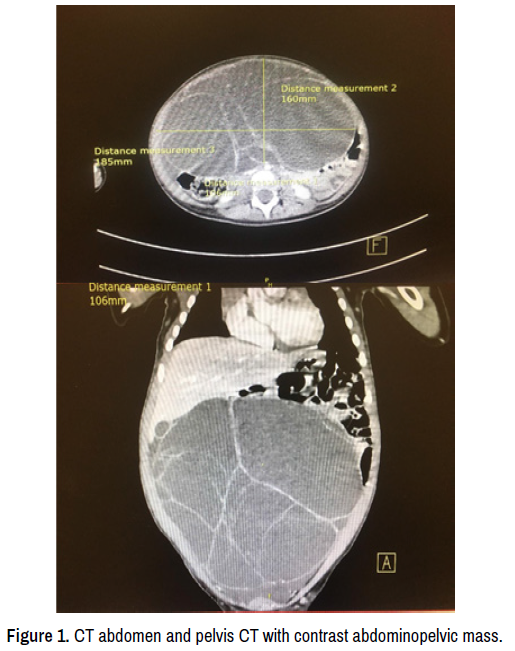

CT abdomen and pelvis with contrast showed an 18 × 16 × 10 cm abdominopelvic mass with no visualization of left ovary suggestion of a left ovarian mass (Figure 1). The patient underwent a left salpino-oophorectomy and a resection of the big mass (Figure 2). The findings of the histology were compatible with granulosa cell tumor, juvenile type stage IA according to the International Federation of Gynecology and Obstetrics (FIGO) system (Figure 3). During her follow-up, there was a regression of the pubertal signs, the serum estradiol level had dramatically declined to 5 pg/ml, CT abdomen and pelvis with contrast showed no pathological findings after one month of surgery.

Figure 1. CT abdomen and pelvis CT with contrast abdominopelvic mass.